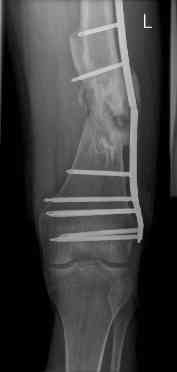

aug 06: blade plate + bone graft

nov 06: revision blade plate

feb 07: retrograde nail + bone graft + BMP

nov 07: persistant non-union distal femur; other fractures healed

uneventfully.